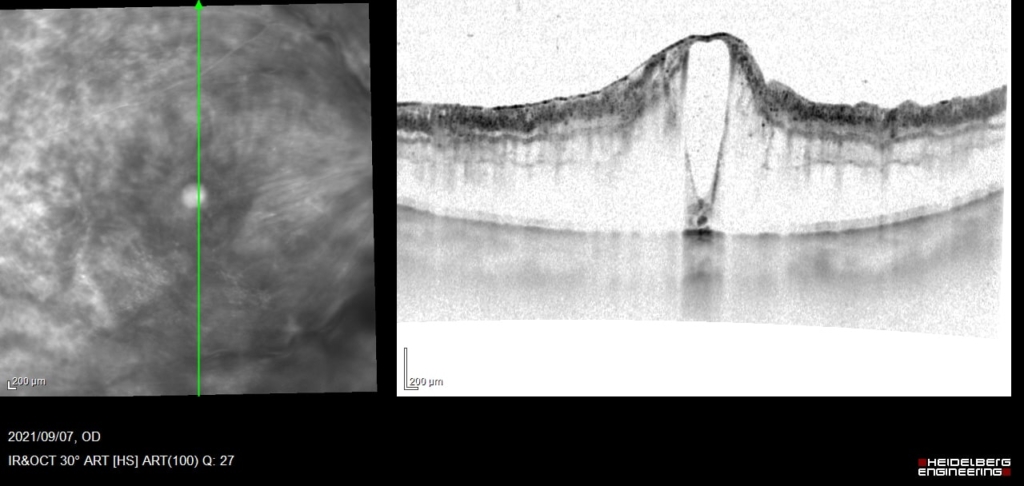

70歳 女性

視力 右眼 0.15(0.3p×+0.25=c-0.75A40°)

主訴 右眼 徐々にかすむ

既往歴 30年前からの糖尿病(HbA1c:7.4)

受診直後より抗VGEF(ラニビズマブ)の硝子体注射を4wおきに施行。

視神経乳頭中心に放射状に静脈に沿って火炎状・線状出血が網膜全体にみられる。